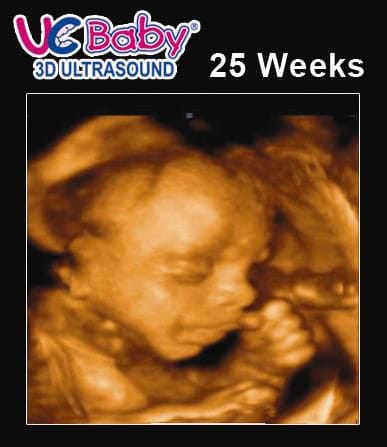

25 Weeks 3d 4d Hd Live Ultrasound